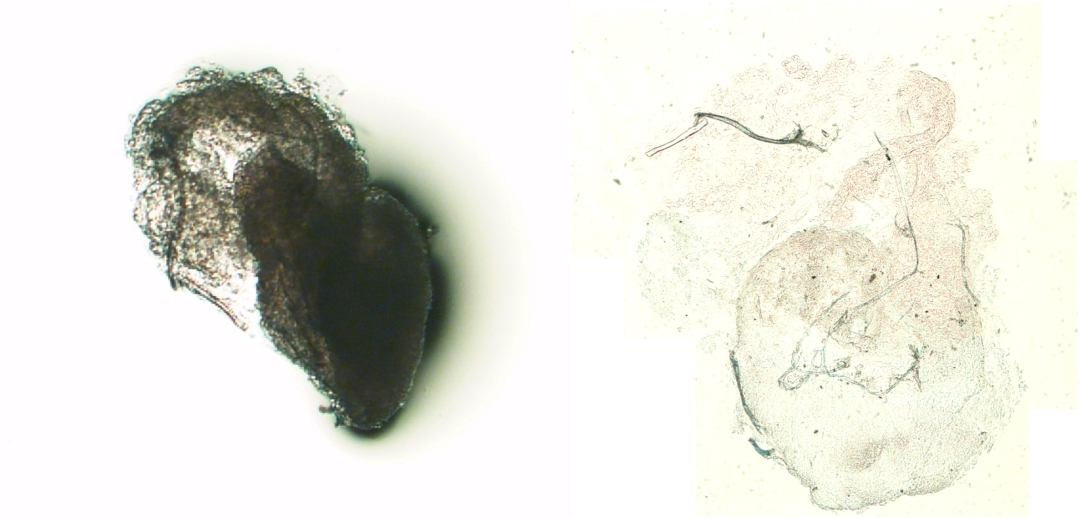

于是我们进行了仔细的眼科检查,发现她眼睛里有很多飘浮的颗粒;又取出她的眼内液体进行了光学显微镜的染色涂片,发现有菌丝还有孢子。之后进一步地证实,发现确实是真菌——但为时已晚,真菌已经在眼睛里造成了严重的组织破坏。

这张图就是一位真菌感染的患者的眼睛。他白内障术后出现了视物模糊。我们发现(1,3)-β-D-葡聚糖的检测强阳性,于是就积极地进行了抗真菌治疗,最后他眼睛里的“蘑菇”消失得无影无踪,保住了视力,恢复了光明。